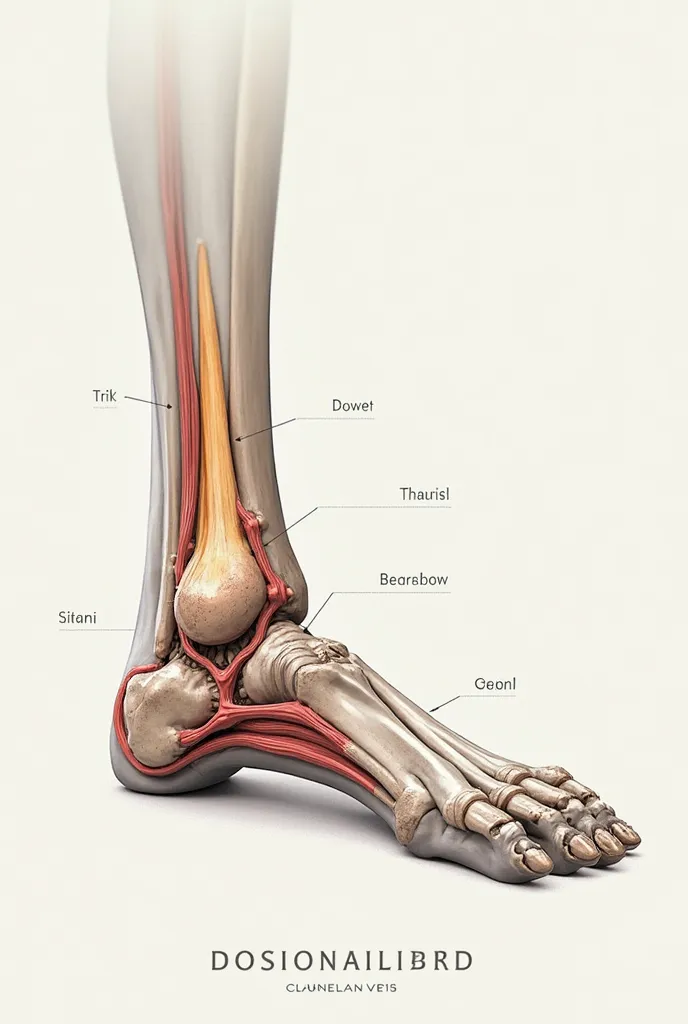

A close up of a white object with a human leg

Close-up of human knee,There is a bone in the middle, knee, Knees, surreal bone structure, Protruding bones, Realphotos, orthographic view, Look across the shoulder, medical depiction, Osteoarticular joints, computer generated, hyper realisitc, sharp bone structure, joint, digital painted

medical depiction

Osteoarticular joints

sharp bone structure